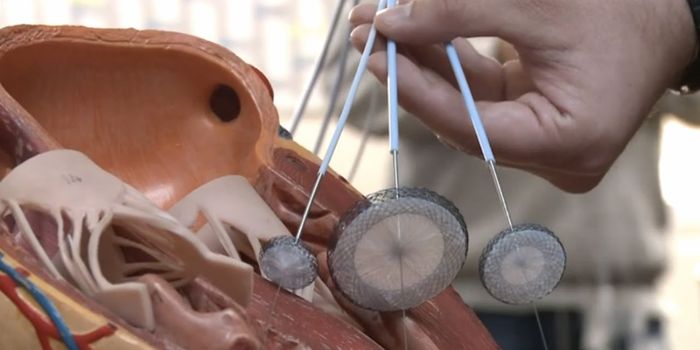

DEC 26, 2015VideosFrom Saint Mary's Hospital in Waterbury, Connecticut, Chief of Cardiology Dr. Paul Kelly briefly discusses how the newes ...

FEB 23, 2019CardiologyThe circulatory system is a complex collection of the heart and its many chambers, and the vessels that move blood aroun ...